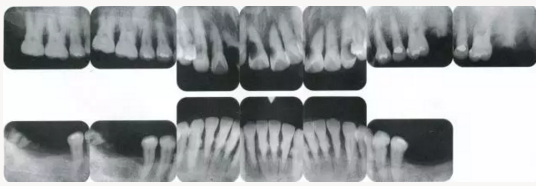

22222222222222222222222222.png

▲圖19-4

X光片。牙槽骨明顯缺失。